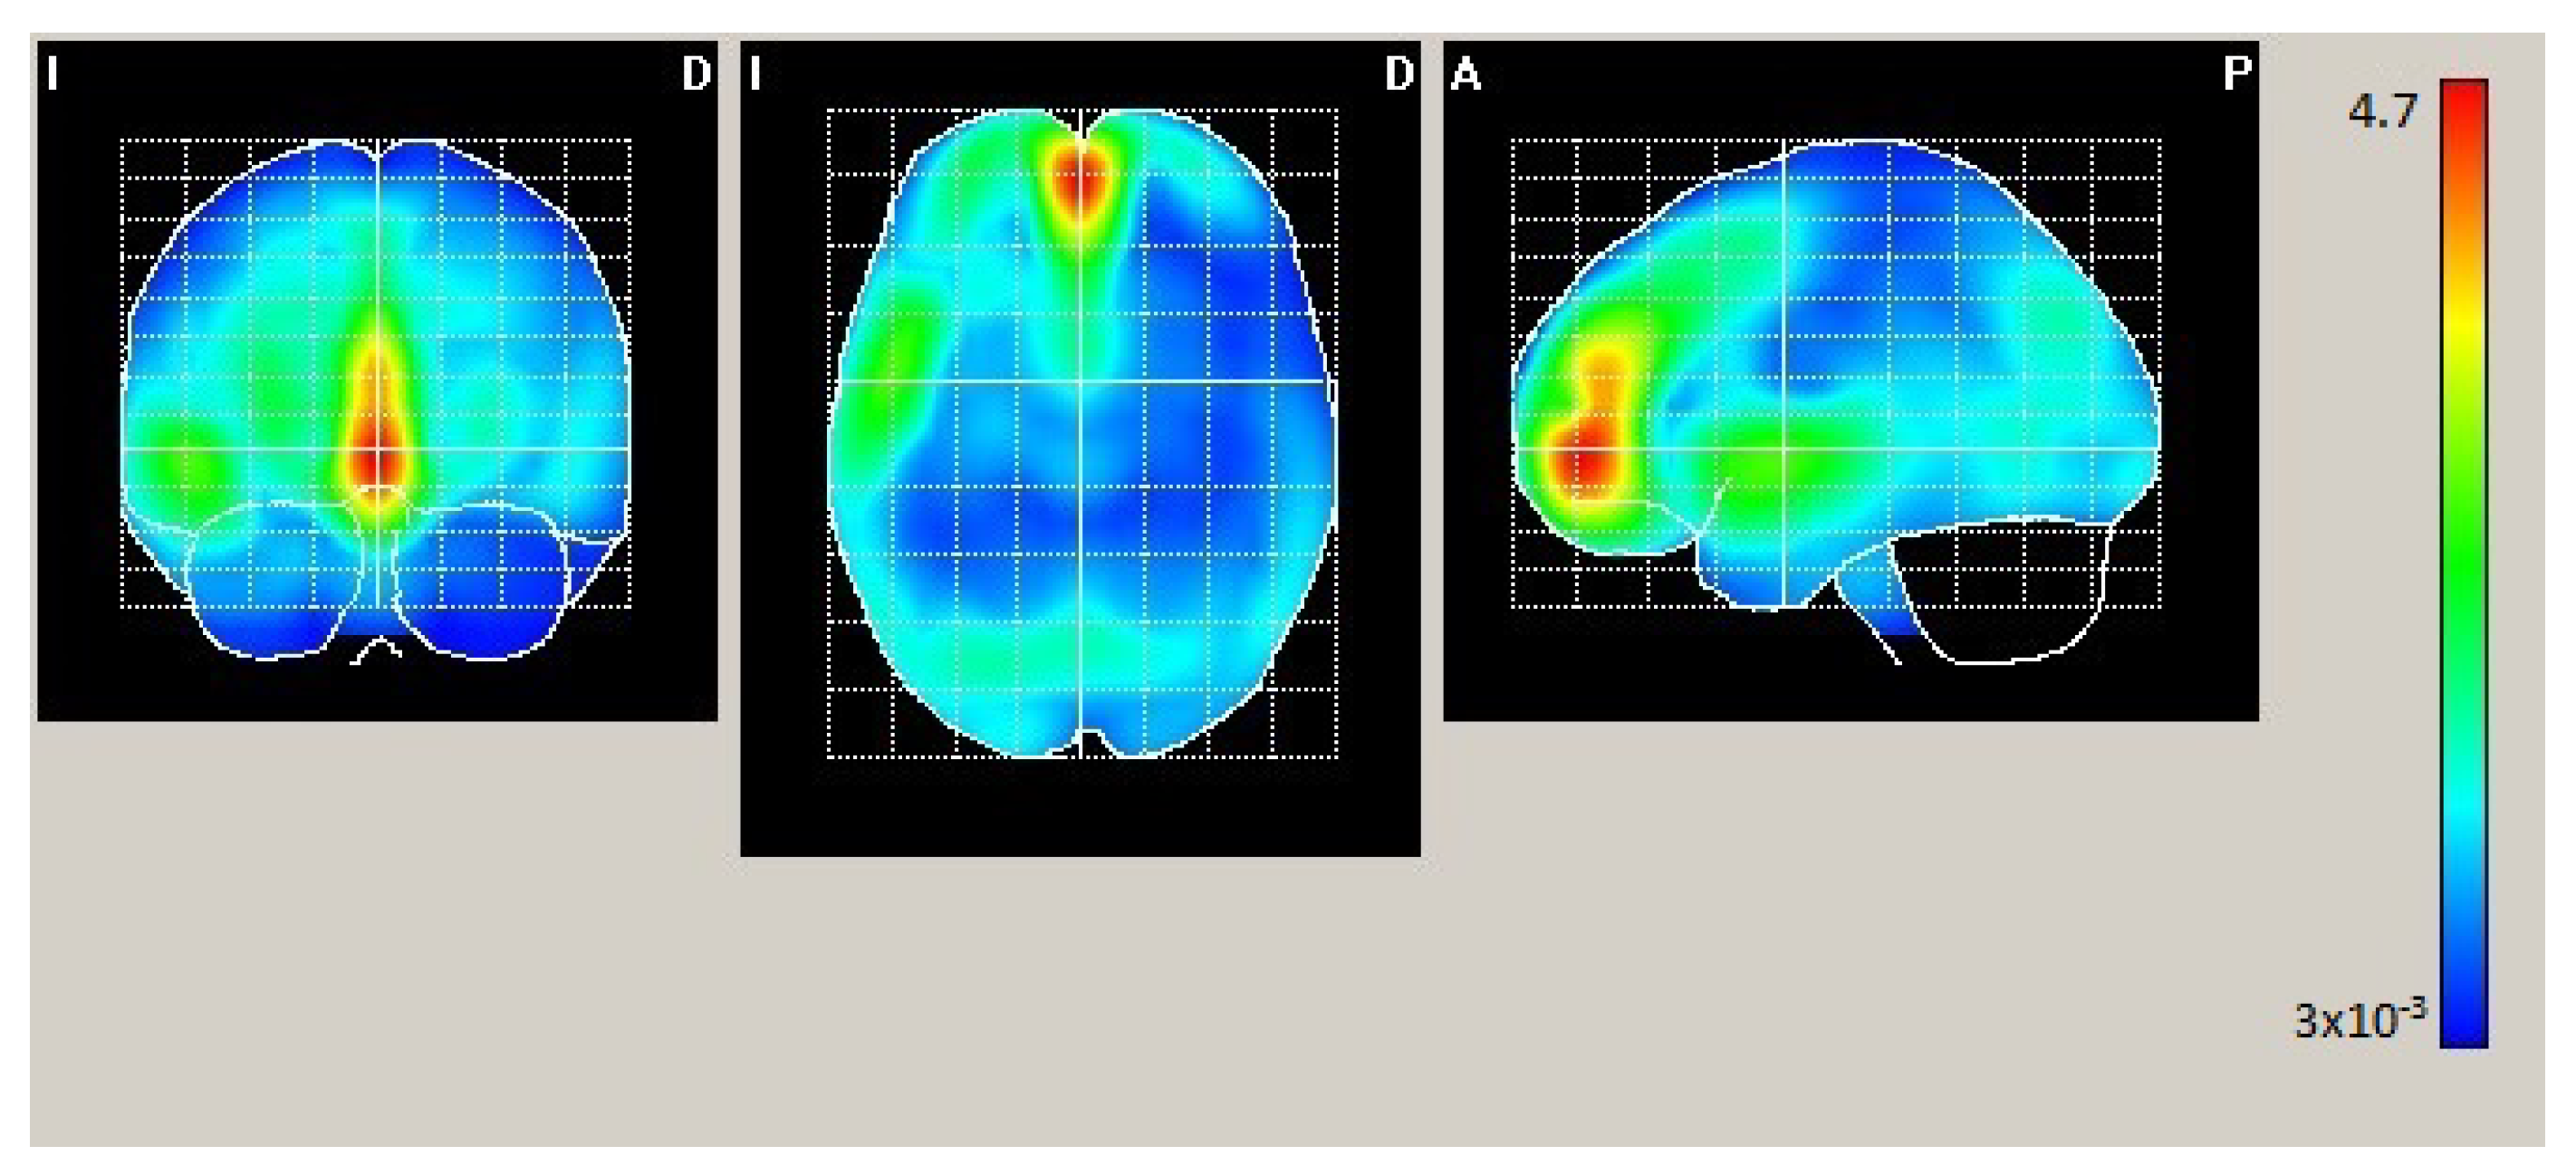

In Condition 3 (hearing-impaired participants and visual and vibrotactile stimulation), as shown in Figure 4 and Table 4, maximum statistically significant activation was found in the bilateral middle frontal orbitofrontal, bilateral superior frontal gyrus, and left cingulum. In a remarkable comparison of Figure 2 and Figure 4, the difference apparently lies in the scale only.

Figure 4.

Mean electrical maps for Condition 3 (hearing-impaired participants, visual stimulation). Maximal intensity projection areas are displayed in yellow/red color. SPMs were computed based on a voxel-by-voxel Hotelling T2 test against zero.

In Condition 3 (hearing-impaired participants and visual and vibrotactile stimulation), we again found peak activation in the bilateral middle frontal orbitofrontal, bilateral superior frontal gyrus, and left cingulum, which are all the same activation areas as those found in Condition 1, but with a remarkably higher statistically significant activation (see scale in Figure 4). The middle frontal gyrus is noteworthy because, as cognitive processes progress, emotions are increasingly processed in the right hemisphere [64,65].